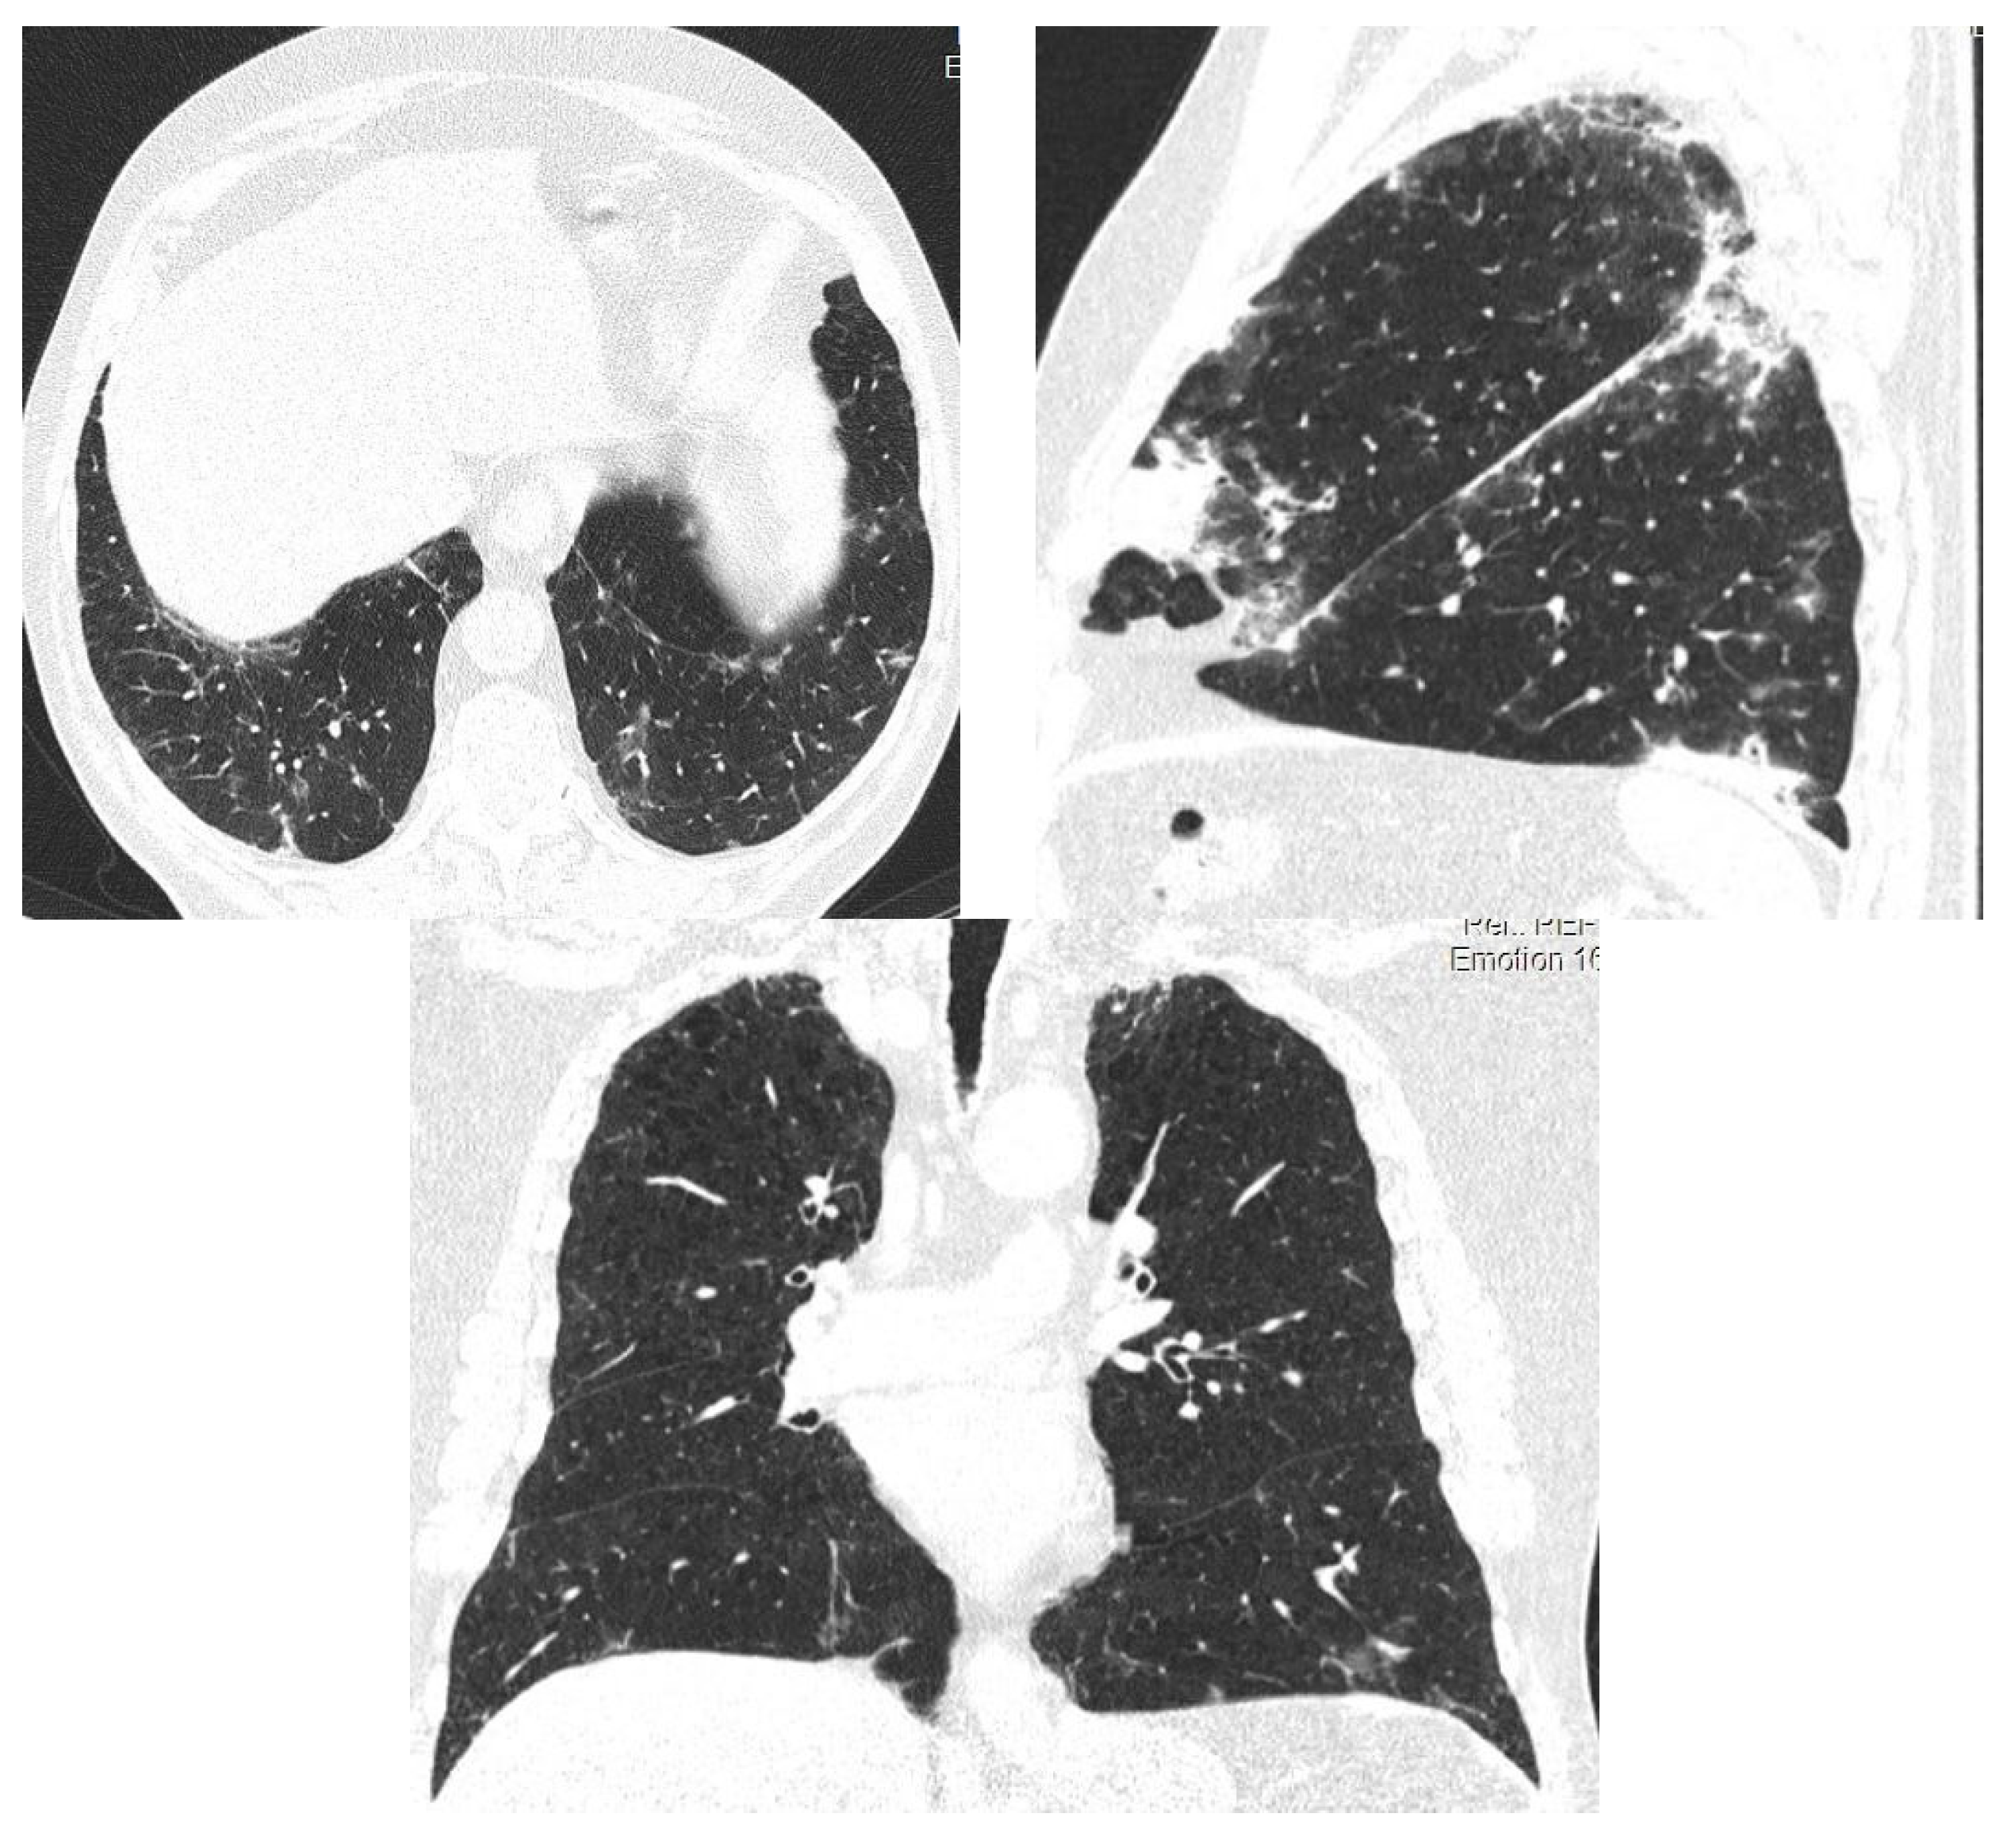

2.2. Case Presentation 2